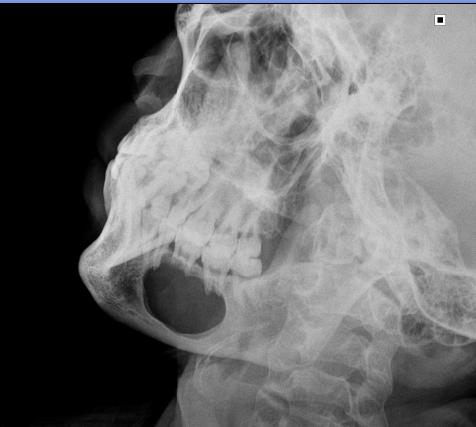

以下是引用吴教授在2010-6-20 14:53:00的发言:[br]右侧下颌骨见单房状较大囊状透光区,期内未见未见间隔,牙根部分吸收及受压移位,我考虑;2造釉细胞瘤可能性大。2不除外颌骨囊肿。

以下是引用拾荒者在2010-6-20 20:44:00的发言:[br]下颌囊状透亮影透光度较好,密度均匀,无分隔,囊壁光滑完整,无分叶及切迹,囊内有正常牙根及牙根吸收表现,首先考虑巨大根尖囊肿;应该与单房型造釉细胞瘤及单房型巨细胞瘤鉴别。